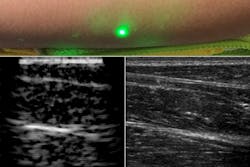

The researchers replaced the acoustic detector of conventional photoacoustic imaging with a 1550 nm continuous-wave laser-Doppler vibrometer to measure skin vibrations (see figure). This makes for a fully noncontact system, nearly eliminating the risk of repetitive-stress injuries for sonographers. The selection of wavelengths around 1550 nm allows the system to take advantage of advances in telecommunications technology, as well as matching tissue characteristics. In addition, the power and energy required by the LUS system are well within laser-exposure safety limits for human use.

The researchers validated their method on tissue phantoms with embedded metal features, porcine tissue, and human forearms, where the reconstructed images were consistent with traditional ultrasound images. The LUS images are comparable to circa-1960s ultrasound, prior to the electronics and manufacturing improvements that led to the rapid, high-quality imaging of contemporary ultrasound. Xiang (Shawn) Zhang, a researcher and author on the MIT team, noted that “early-stage ultrasound images were generated using a single transducer that was manually moved to generate an image, which is very similar to our present LUS, since we are moving laser spots on the skin surface. The system should benefit from an innovation pathway similar to that responsible for the past 50 years of traditional ultrasound development.” Advances in silicon photonics, for example, could lead to the development of multipoint light sources comparable to the piezoelectric arrays of traditional ultrasound.